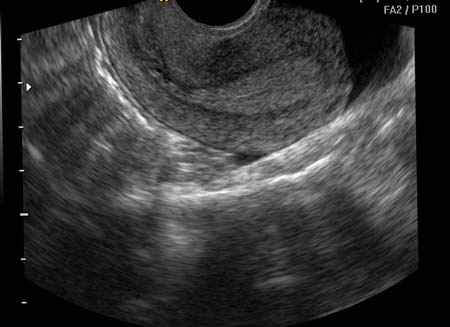

УЗИ

Ультразвуковое исследование, проводимое при подозрении на рак шейки матки, позволяет увидеть специалисту на мониторе, что матка приняла бочкообразную форму, видно, что региональные лимфоузлы увеличены в размерах. На узи также виден неровный контур шейки матки.

По узи врач смотрит на состояние шейки матки, проходимость цервикального канала, сравнивает полученные результаты с имеющимися показателями нормы. Диагностическое исследование может быть выполнено 3-мя способами:

- через прямую кишку (трансректально) – предварительно за 6 часов проводиться очистительная клизма;

- через стенку живота (трансабдоминально) – пациентка выпивает за 1 час до исследования 1 л воды, также сутки соблюдается бесшлаковая диета;

- через влагалище (трансвагинально) – специальной подготовки исследование не требует.

Если во время исследования обнаруживается отклонение от нормы, специалист может назначить дополнительные диагностические методы.